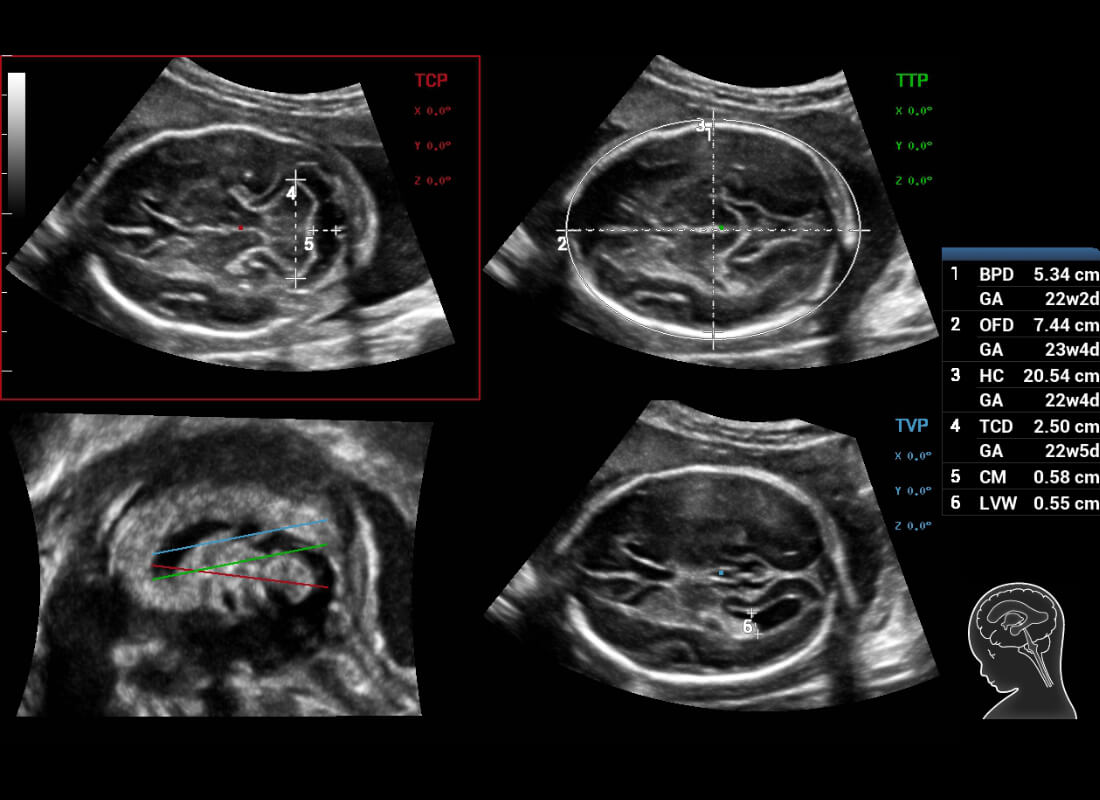

Central nervous system (CNS) malformations are one of the most common congenital abnormalities. Unfortunately, due to imaging limitations such as poor fetal position, acoustic shadowing, and operatorsŌĆÖ poor scanning skills, the MSP is particularly difficult to find in a 2D ultrasound. In this case, a faster and more user-friendly method, which automatically displays the standard planes together with the required measurements in a fetal CNS examination, could significantly boost both the quality and efficiency of clinical diagnoses.?NuewaŌĆÖs intelligent solution of fetal brain can realize automatic acquisition of brain volume data based on intelligent recognition of CNS application scenarios, intelligent generation of four fetal brain standard planes including MSP, automatic measurement of CNS biological items and automatic evaluation of fetal brain volume. More importantly, Nuewa's leading color Doppler technology can provide a clear and sensitive dynamic display of blood flow in the tiny vessels.